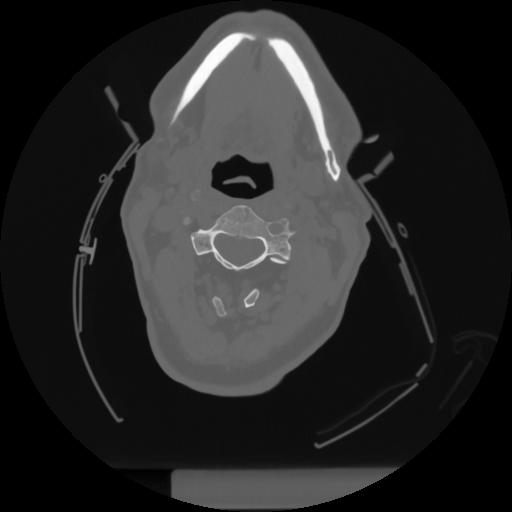

12 P.BLANDAS,,Vol,0.5,P.BLANDAS,,